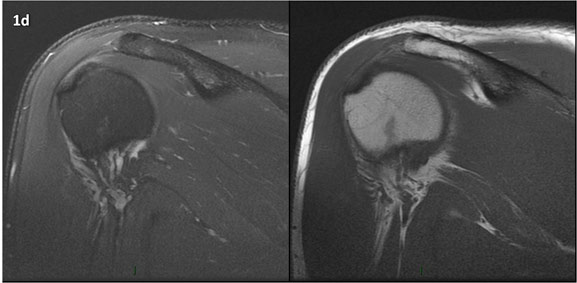

Figura 1 (a-g): Imagens consecutivas de RM no plano coronal nas ponderações DP com supressão de gordura (DP SG) à esquerda e T1 à direita. Clique na seta para passar as imagens.

Figura 1a’ mostrando rotura parcial articular na inserção do supraespinhal (setas azuis).

Figuras 1b’ a 1g’ mostrando atrofia da porção superior do músculo redondo menor (seta salmão), com lipossubstituição mais evidente das mais fibras laterais (seta amarela). As fibras mais inferiores e mediais têm atrofia menos evidente.

Repare que estas alterações não são evidentes nas imagens com supressão de gordura.

Chafik et al. também relataram a presença de um pequeno nervo motor acessório em número variável que se insere na porção lateral do músculo redondo menor. O nervo acessório, ao contrário do principal, tem um curso reto e extra-fascial, sendo menos vulnerável aos efeitos compressivos. De fato, nos casos da atrofia parcial do redondo menor, é mais frequente a atrofia da porção mediodorsal com preservação da porção lateroventral, o que poderia ser explicada pela presença do ramo acessório mais lateral do nervo axilar, embora atrofia isolada do componente lateroventral tenha sido reportada em cerca de 17% dos casos de atrofia de apenas uma porção, o que pode ter sido causada por lesão do nervo acessório. No caso do paciente deste mês, a atrofia é mais evidente nesta porção mais lateral e ventral do redondo menor.